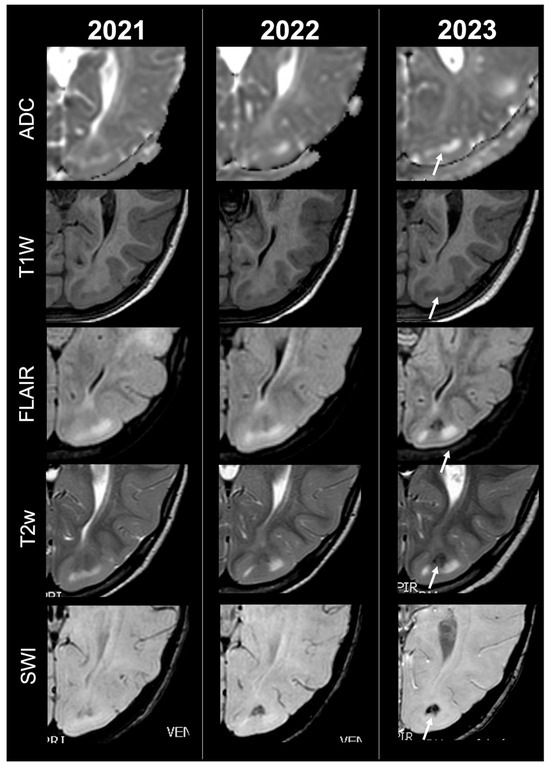

Concerning total lesion count, the interobserver agreement was excellent, with an ICC of 0.91 (95% CI: 0.87–0.95). At baseline, the total number of CTs identified across the cohort was 918 (mean ± SD = 16.1 ± 12.4), whereas at the last available MRI follow-up, the overall count increased to 1070 (mean ± SD = 18.8 ± 13.3), corresponding to a net gain of 152 CTs, equal to a relative variation of +17%. When stratified by tuber type, distinct trajectories were observed over time. Type A CTs, which were relatively abundant at diagnosis (N = 303, mean ± SD = 5.3 ± 7.0), decreased to 255 (mean ± SD = 4.5 ± 5.9) at follow-up, yielding a reduction of 48 lesions (−16%). Conversely, type B CTs showed an opposite trend, increasing from 438 (mean ± SD = 7.7 ± 8.4) at baseline to 556 (mean ± SD = 9.8 ± 8.6) at follow-up, corresponding to a net increase of 118 tubers (+27%). An example of MRI signal evolution from tuber A to tuber B is shown in Figure 1. Similarly, type C1 CTs rose from 160 (mean ± SD = 2.8 ± 4.8) to 220 (mean ± SD = 3.9 ± 5.8), with a net gain of 60 tubers (+38%). Type C2 CTs, initially rare at diagnosis (N = 14, mean ± SD = 0.2 ± 0.8), markedly expanded to 33 (mean ± SD = 0.6 ± 1.5), accounting for an increase of 19 CTs (+136%). Finally, type D CTs were only sporadically encountered, with a modest increase from 3 (mean ± SD = 0.1 ± 0.3) to 6 (mean ± SD = 0.1 ± 0.4), equating to a 100% variation. The observed increment of type C2 tubers was attributable almost exclusively to the progressive transformation of pre-existing type B lesions and, more prominently, type C1 lesions, while the increase in type C1 tubers reflected the gradual conversion of both type A and type B CTs that were already detectable at disease onset. An example of MRI signal evolution from tuber B to C1 is shown in Figure 2, while from tuber C1 to C2 in Figure 3. Only in one patient was a type C1 tuber newly identified at follow-up without clear evidence at baseline. In contrast, newly apparent tubers emerging over time but not clearly visible on baseline scans were most frequently represented by type A and type B lesions. Type D tubers were rare overall and were identified in only six lesions from four patients with a particularly high lesion burden; in all but one case they represented the evolution of type A or type B CTs (an example of MRI signal evolution from tuber A to tuber D is shown in Figure 4), while in a single case they were associated with adjacent subtle calcific foci. Overall descriptive data are summarized in Table 1.

Figure 4.

Left parietal tuber transition from type A to D at three different timepoints in a female patient diagnosed with TSC2.